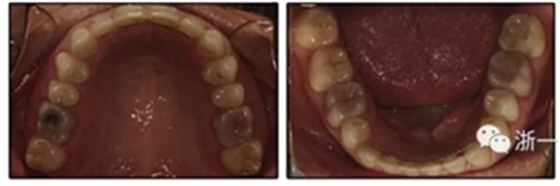

患者是一名39歲的白人婦女,病史不明。她主訴是她的右側(cè)顳下關(guān)節(jié)有不適癥狀,并希望改善她的笑容。她有一個(gè)對(duì)稱的臉型和一個(gè)II類2分類的微笑。她的側(cè)貌是凸的,90°的鼻唇角和骨性下頜骨發(fā)育不足??趦?nèi),上頜中線與面部重合,但下頜中線向右側(cè)偏移5mm;存在6mm的深覆蓋。她的兩側(cè)都是I類磨牙關(guān)系,左側(cè)是I類尖牙關(guān)系,右側(cè)是完全的II類尖牙關(guān)系。下頜右側(cè)第二前磨牙先天性缺失(圖1和圖2)。最初的全景片顯示了足夠的骨質(zhì)水平和全部的第三磨牙(圖3)。治療前的頭影測(cè)量片片和相應(yīng)的頭影測(cè)量圖(圖3)證實(shí)ANB為7°,Wits評(píng)估為6 mm的骨性II類錯(cuò)合(表)。上頜切牙相對(duì)與面部和顱底的位置很好。下頜切牙前傾。診斷為II類2分類錯(cuò)合畸形,伴有骨性下頜發(fā)育不足,右側(cè)顳下頜關(guān)節(jié)癥狀,下頜中線向右側(cè)偏移5mm,先天性右下第二前磨牙缺失。

圖3. 治療前頭影側(cè)位片,頭影測(cè)量描跡圖和全口X光片